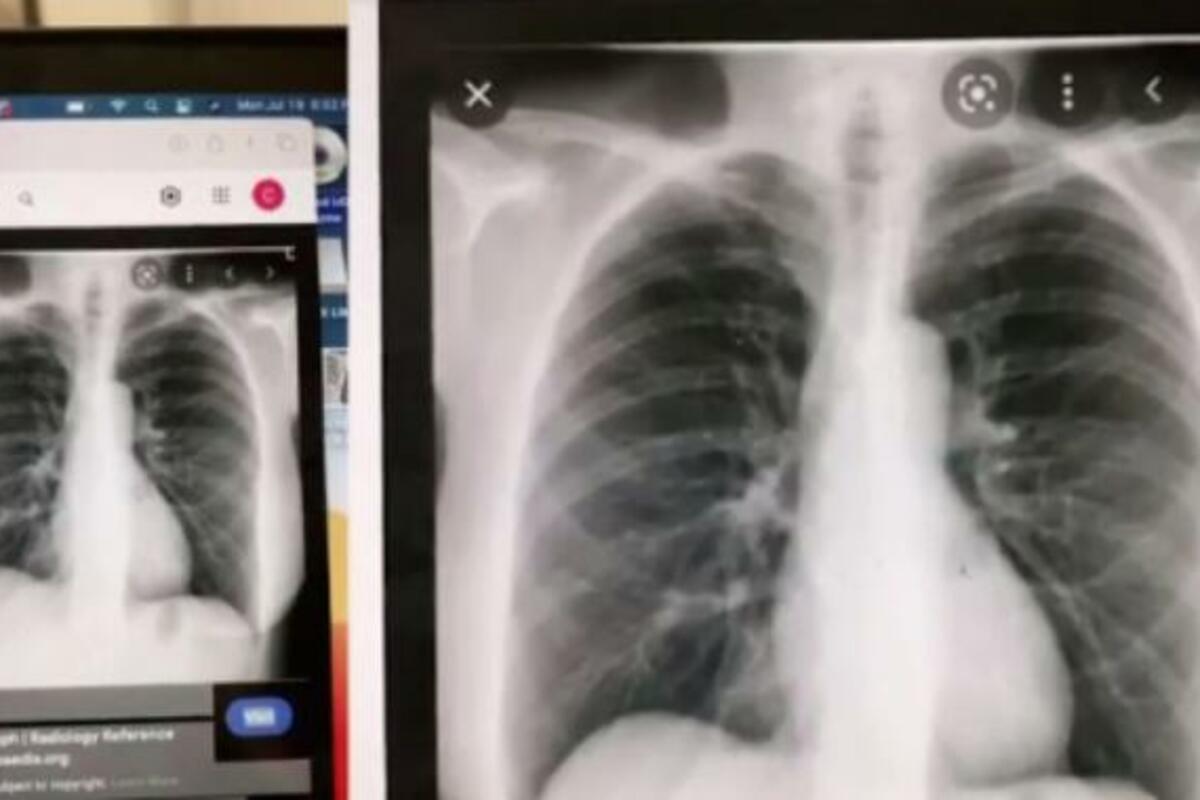

Nakon što se posekla na bodljikavu žicu, došla je kod lekara da primi tetanus. Tamo su lekari primetili da jako kašlje, pa se požalila na česte prehlade. Napravili su rendgen kako bi proverili ima li infekciju pluća, a ono što su videli na nalazima ih je iznenadilo. Lekar ju je pitao zna li da je njeno srce na suprotnoj strani nego što je uobičajeno, a Kler je rekla da to prvi put čuje.

- Saznala sam ovo tek s 19 godina... Iako, jednom sam bila na pregledu kod svog lekara i rekao je da mi se srce jače čuje na desnoj strani. Ipak, ne možete tek tako postaviti ovu dijagnozu koja je prava retkost - priča Kler koja je svoju situaciju ispričala na TikToku i postala viralna - pogledalo ju je više od 3 miliona ljudi, prenosi The Sun.

- Dekstrokardija nije opasno stanje - ako do sada nije imala nikakve smetnje, verovatno niti neće, tvrde lekari.